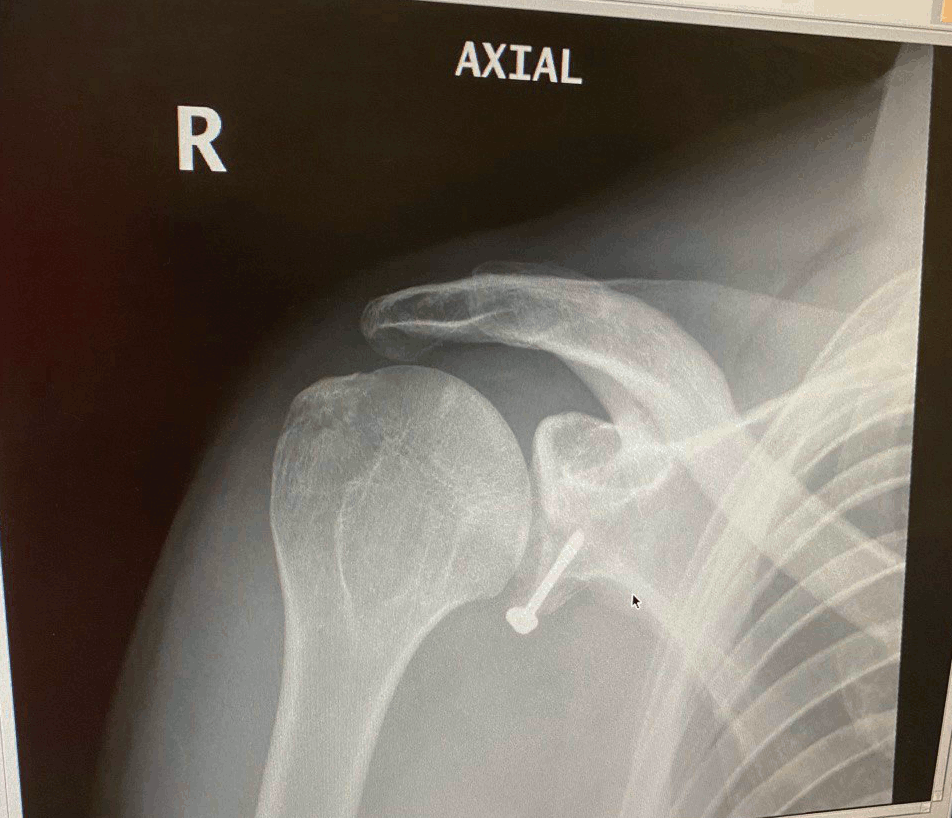

It's been quite a while since my last post in fairness, many things happened in the meantime like breaking a humerus first and a glenoid twelve weeks after, I really pushed my rollerblading skills a tad too much the past summer!